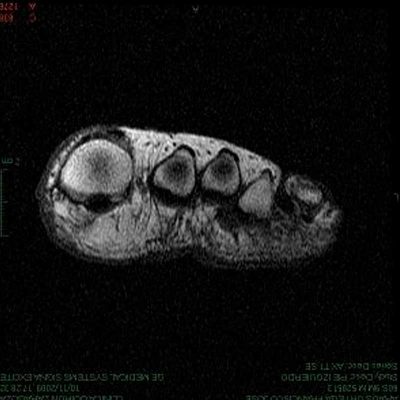

METATARSALGIA.

Término que hace referencia al dolor en la región anterior del pie, preferentemente plantar y muy relacionada con la carga que reciben nuestros huesos metatarsianos, y que constituye uno de los dos pilares de sustentación (antepié) junto con el talón (retropié). En la mayoría de los casos se trata de una afección de origen mecánico relacionada con nuestra anatomía, peso, actividad, antecedentes personales y calzado. El peso de una persona se distribuye por toda la planta del pie y es en el momento propulsivo de la marcha cuando la carga se desplaza hacia el antepié. Si tenemos un antepié con una estructura metatarsal equilibrada, el reparto de la carga será uniforme, pero cuando la carga se reparte de forma diferencial concentrándose en uno o alguno de los metatarsianos se produce una sobrecarga selectiva que puede suponer un estrés de los tejidos del propio metatarsiano o de cualquiera de las estructuras blandas que se sitúan bajo éste. En función de la estructura dañada, el origen de la metatarsalgia podremos encontrarlo en la piel (p.ej. callo), en un ligamento (ej. rotura del ligamento plantar), en un tendón (tendinopatía flexora), en la cápsula articular (capsulitis), en un nervio plantar (neuroma), etc. Pero la metatarsalgia puede formar parte de un proceso inflamatorio local (traumatismo) o sistémico (ej. artritis reumatoide).

Al diagnóstico de la lesión llegamos a través de la anamnesis en la que resulta de especial relevancia las circunstancias que rodean al paciente como el peso, la actividad, el tiempo que permanecemos de pie. Los hábitos en la deambulación. Los deportes que realizamos y muy especialmente el calzado, que en muchas ocasiones puede ser el desencadenante del problema y al mismo tiempo el primer eslabón del tratamiento. En el diagnóstico a las pruebas complementarias como la radiografía convencional, la ecografía, la RMN o la gammagrafía ósea resulta imprescindible los análisis podobarométricos que miden el reparto de la fuerza del peso durante la deambulación, la marcha, la carrera y el salto. Estos estudios que realizan un enfoque cinético se completan con estudios cinemáticos que ayudan a comprender la etiopatogenia de la lesión.